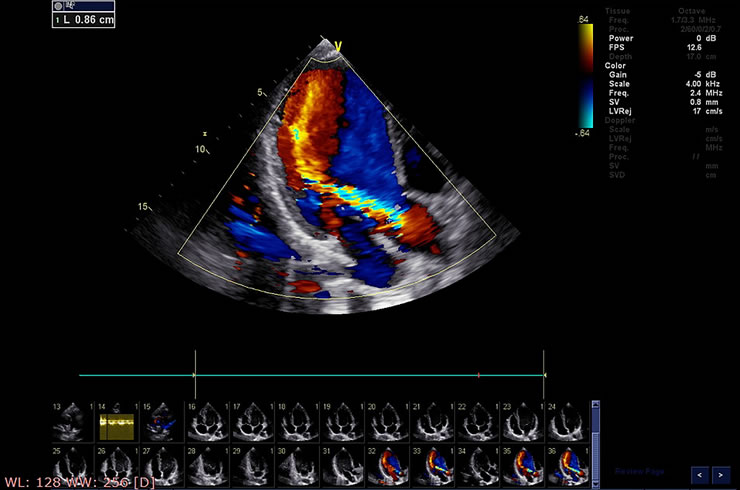

Μη επεμβατική απεικόνιση

Η υπερηχοκαρδιογραφία ή καρδιακή μαγνητική τομογραφία μπορεί να πραγματοποιηθεί για την αξιολόγηση της καρδιακής λειτουργίας και τον εντοπισμό περιοχών βλάβης.